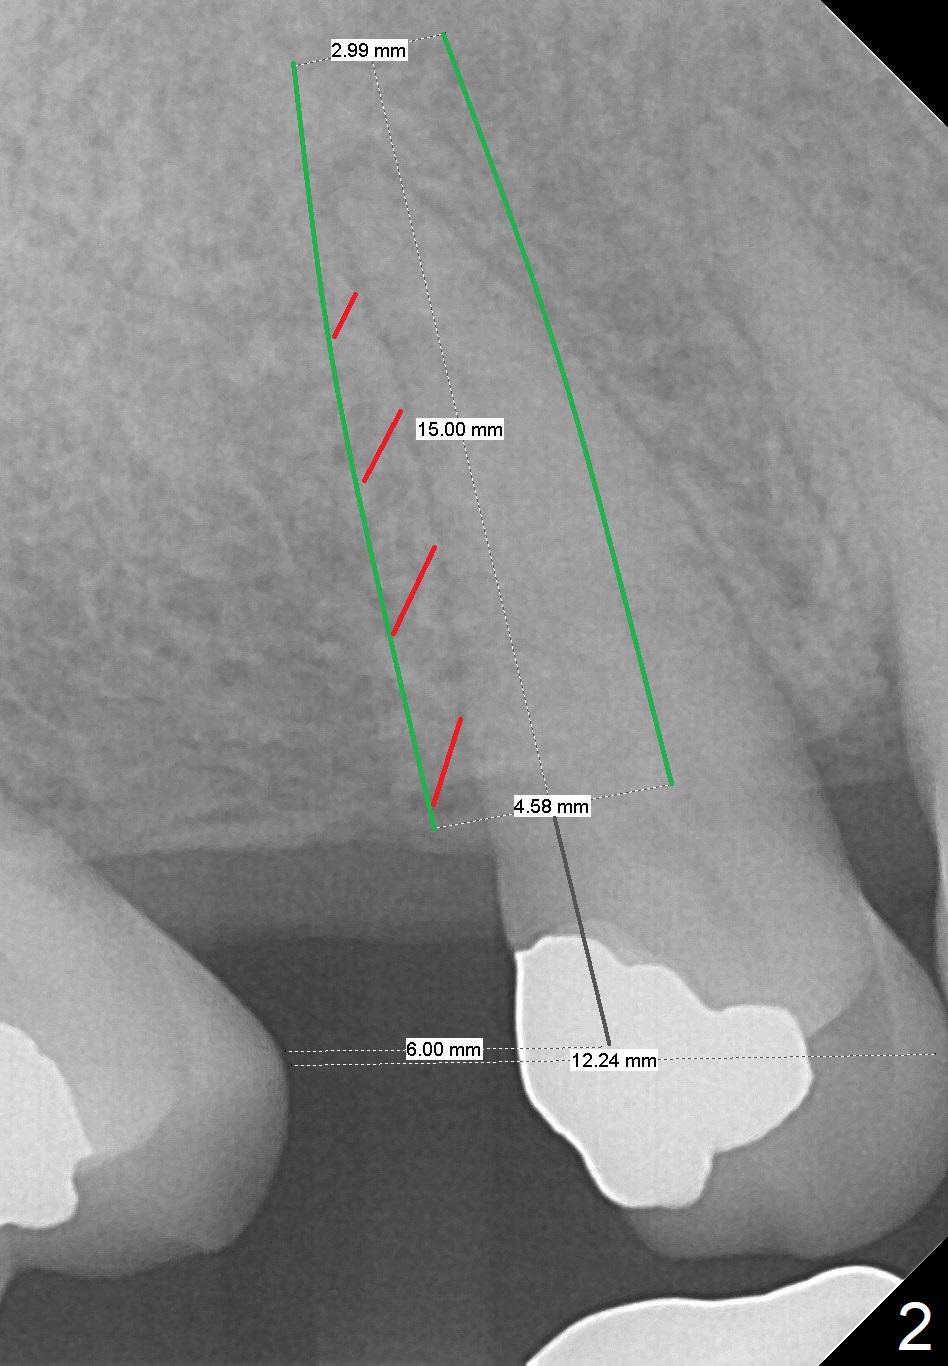

A 62-year-old man has sudden severe pain associated with the tooth #4. Since the edentulous space at #3 is narrow (Fig.1,3), an implant is placed distal to the site of #4 (after extraction) as a molar (Fig.2-4). Use Lindamann bur to remove the bone in the distal wall of the socket prior to osteotomy (Fig.2 red dashed area).